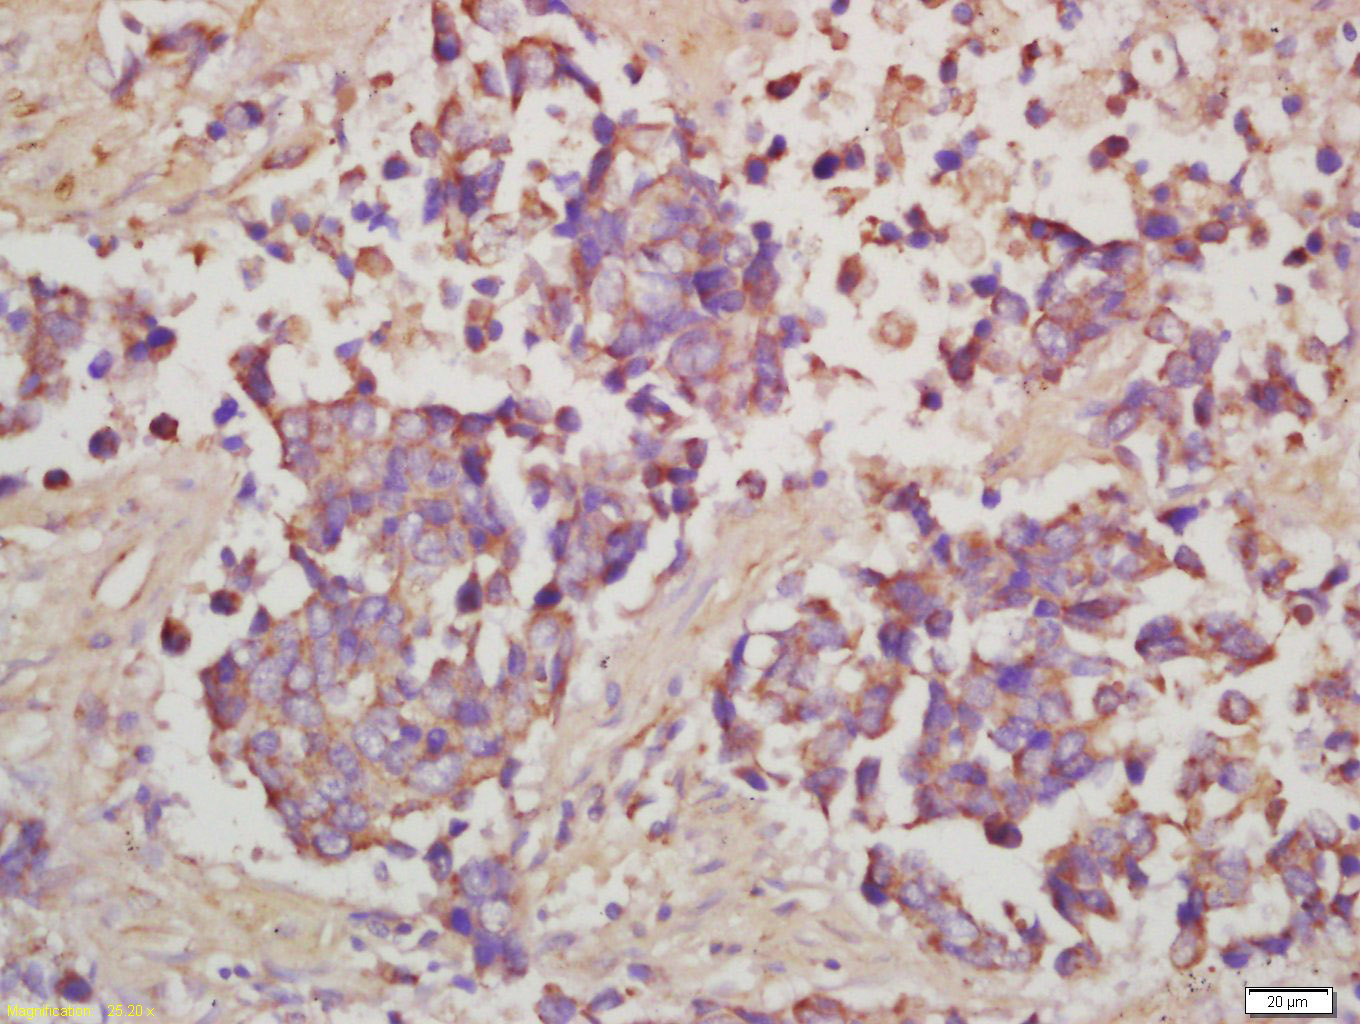

Tissue/cell: human lung carcinoma; 4% Paraformaldehyde-fixed and paraffin-embedded; Antigen retrieval: citrate buffer ( 0.01M, pH 6.0 ), Boiling bathing for 15min; Block endogenous peroxidase by 3% Hydrogen peroxide for 30min; Blocking buffer (normal goat serum,C-0005) at 37℃ for 20 min; Incubation: Anti-Phospho-RPS6 (Ser240+Ser244) Polyclonal Antibody, Unconjugated(bs-3389R) 1:200, overnight at 4°C, followed by conjugation to the secondary antibody(SP-0023) and DAB(C-0010) staining